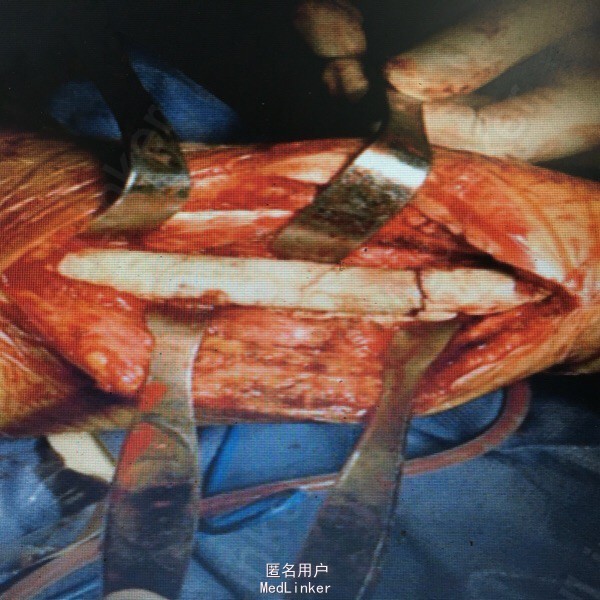

女性患者,43岁,因交通伤致右尺桡骨开放性骨折,当地医院行清创、骨折切开复位内固定术,术后尺侧切口反复红肿、流脓,经换药治疗4个月前臂仍疼痛、畸形、功能受限,X线片(A, B);第1阶段手术探查明确诊断(感染范围、程度及细菌种类),桡骨重新复位、内固定、恢复力线、间接稳定尺骨,尺骨骨折断端清创、抗生素骨水泥占位器置入(C),术后X线片(D, E);全身及局部应用敏感抗生素;第2阶段膜诱导技术修复骨缺损;切开诱导生成的生物膜,取出骨水泥占位器,钢板固定骨折(F, G);髋臼锉取骨技术获取粉碎松质骨、皮质骨混合颗粒,锁定钛板内固定和愈合片子(H, I)